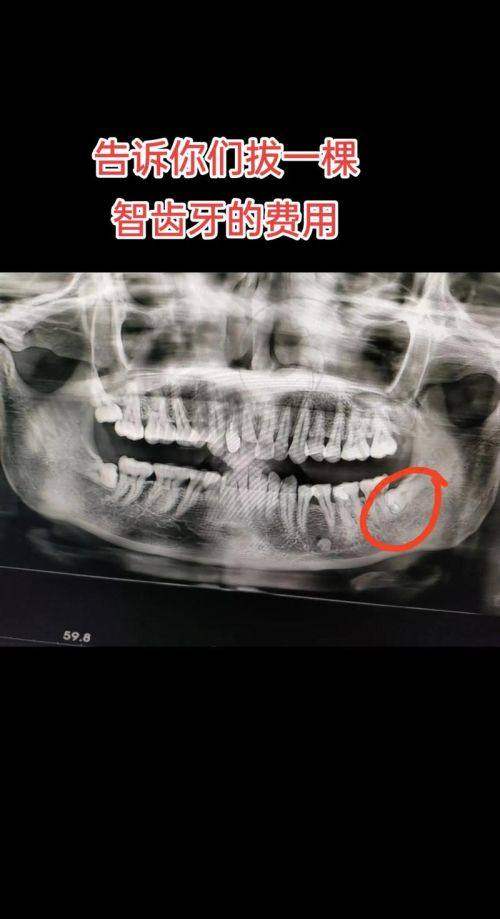

横生智齿拔除“水特别深”:有人花500元轻松搞定,有人花2000元还遭了罪。关键是要避开“低价陷阱”和“技术盲区”。结合2025年全新行业动态,给大家总结了这份“避坑 + 实操手册”,收藏好!

4.1 价格避坑:500 - 2000元/颗差别在哪?别被“低价引流”套路了!

? “某私立医院广告说拔智齿99元,去了却要收1500元,是被骗了吗?”横生智齿拔除价格主要取决于难度等级和技术设备,正规医院的收费明细会包含:术前检查(CT 200 - 500元)、麻醉方式(普通麻醉100元,STA麻醉300元)、手术费(简单横生500 - 800元,复杂埋伏1000 - 2000元)、术后用药(200 - 300元)。